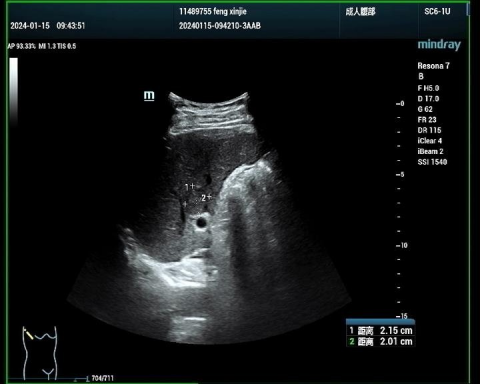

甲状腺癌病例